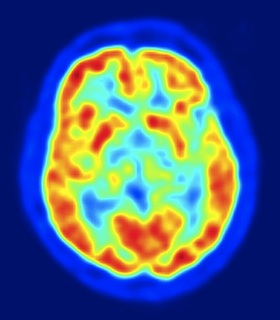

Activity 1: Brain Death - when there is conflicting evidence.

Activity 1: Brain Death

It can be used to focus the students' attention on how we know what death is, particularly brain death. The story can be naratted factually and then in a class discussion, students look at the different points of view; the parents as well as the medical institution.